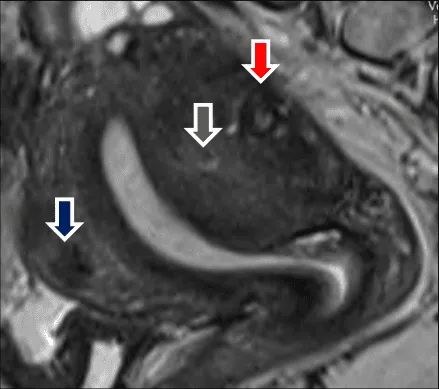

Hình ảnh “Cộng hưởng từ của adenomyosis”.

Tổn thương có thể khu trú tạo giả u xơ, hoặc kết hợp với u xơ thật, khó phân biệt.

Hình ảnh “Kết hợp adenomyosis và u xơ tử cung”.